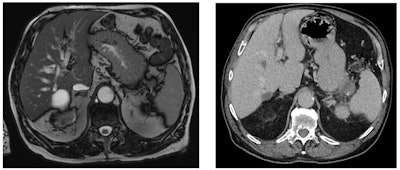

On two scans taken six months apart, a pancreatic tumor (stage IIIA) was missed, with the lesion being visible on review. Low attenuation area proximal body and minimal pancreatic duct dilatation distally were not reported. Figure courtesy of Dr. Nosheen Umar.There is often only a very short period for curative surgery in pancreatic cancer, meaning it is vital that patients are diagnosed with the disease as early as possible, she said. Also, it would be "interesting to know how many outcomes would be different with earlier age detection," noted Umar.